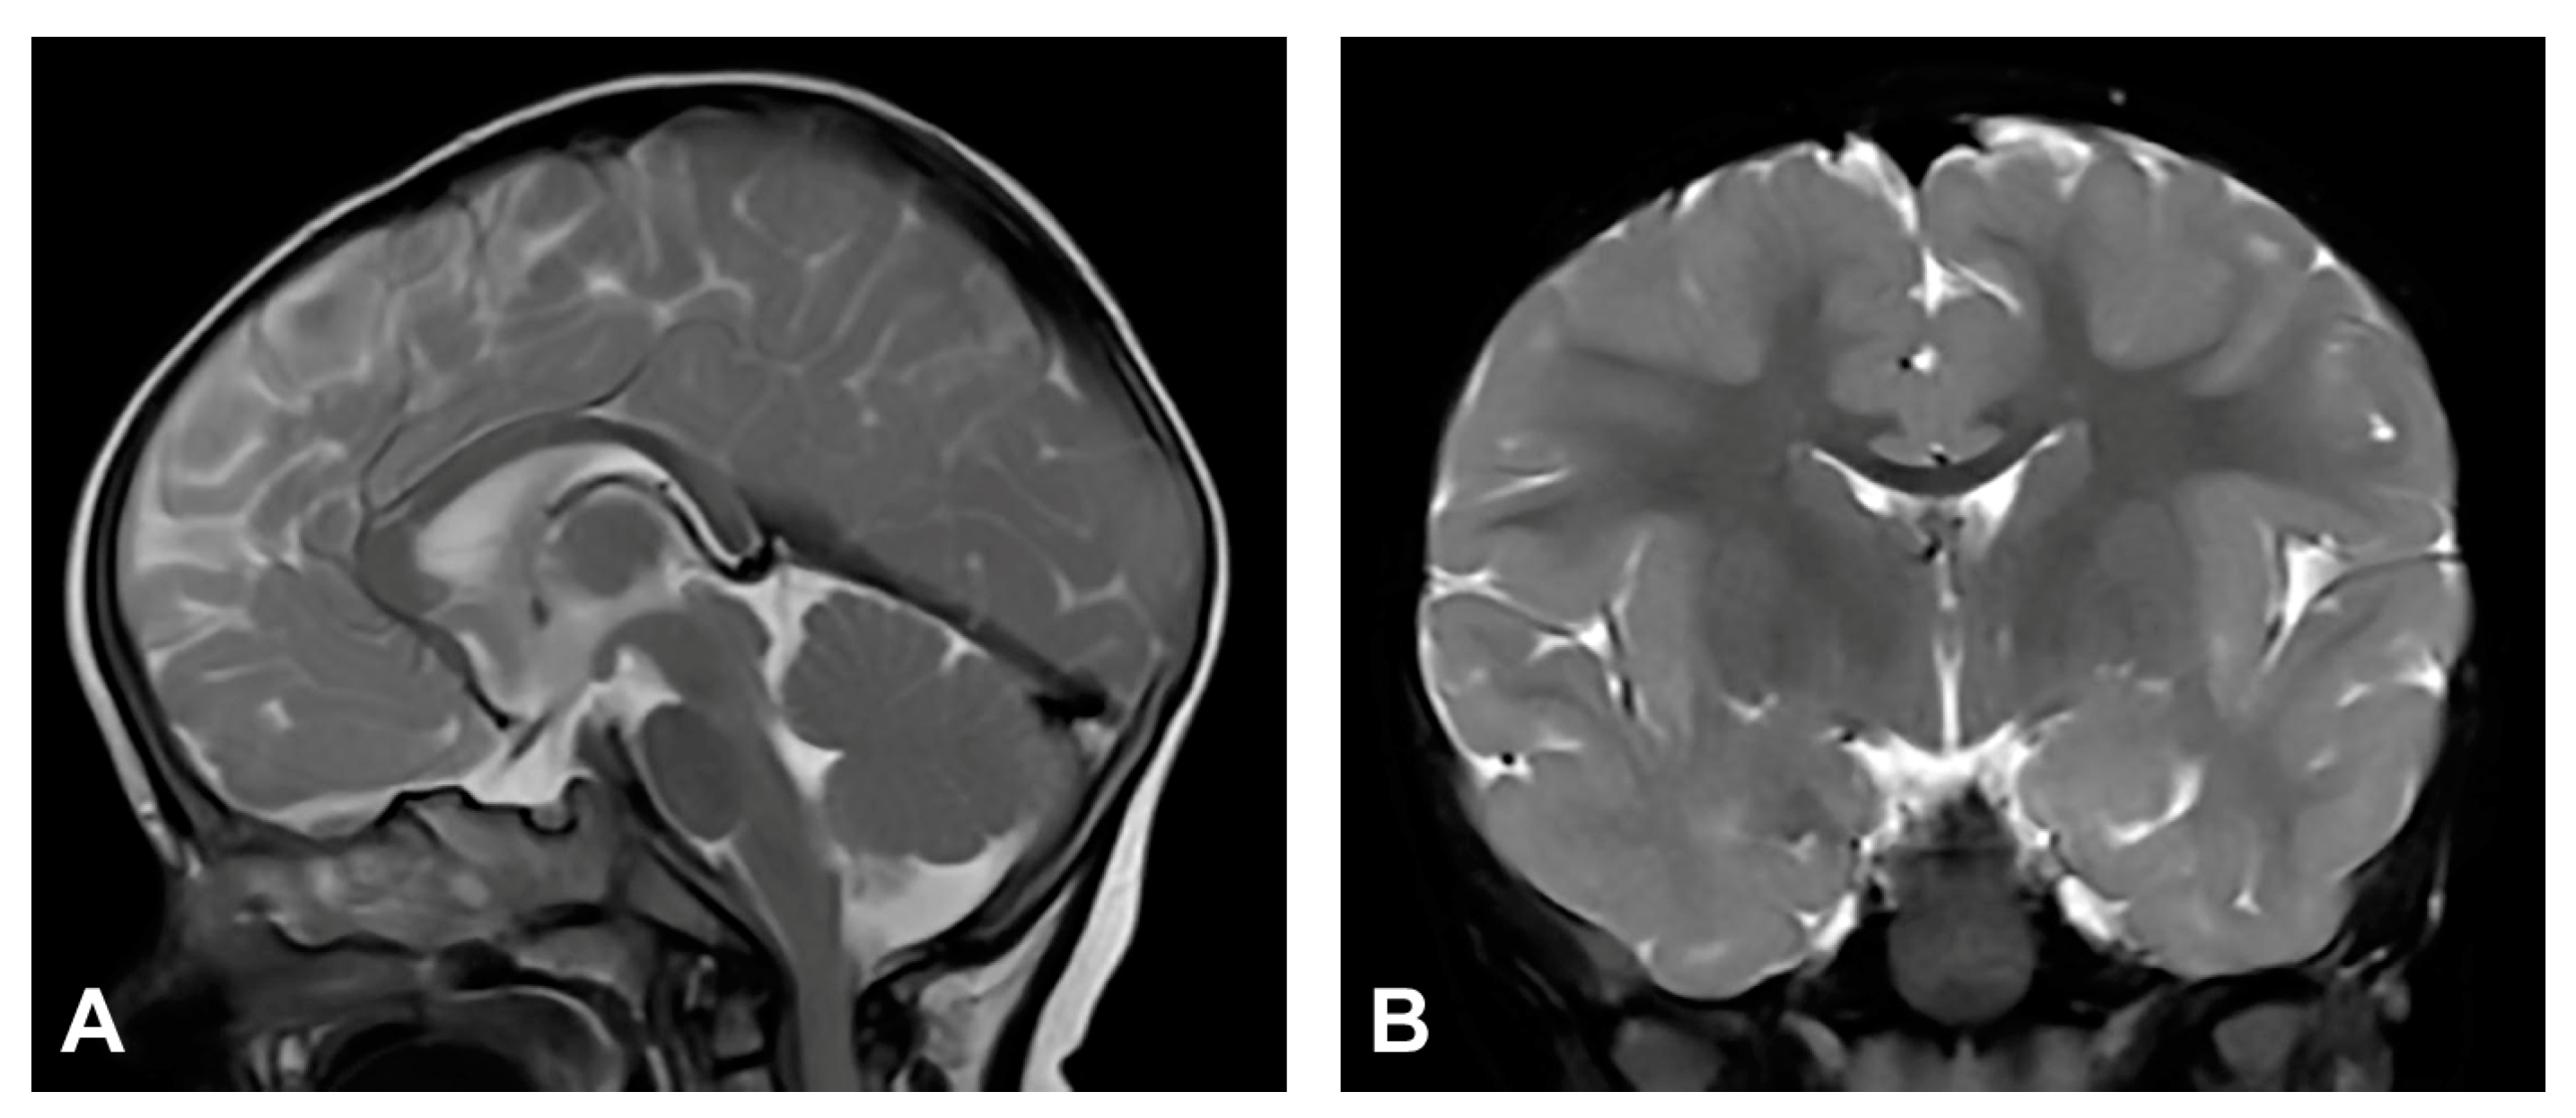

(Case 4) (A) Sagittal and (B) coronal T2W magnetic resonance images at the age of nine months without pathological findings.

3.2.5. Case 5

Upon birth, the patient presented hyperpigmented and verrucous skin changes along Blaschko lines corresponding to stages II and III of IP. Histopathological analysis of skin biopsy confirmed IP. The patient also presented a gothic palate and peg-like teeth. Besides the patient, IKBKG exon 4–10 deletion was genetically confirmed in the patient’s mother. The patient was diagnosed with retinopathia prematuri, and anti-VEGF therapy was administered. Developmental milestones were within the physiological range and neurological development was normal. The patient could sit and walk unsupported and pick up objects with a pincer grip. EEG showed focal epileptic activity but without seizures. MRI showed no pathological findings (Figure 5).

Figure 5.

(Case 5) (A) Sagittal and (B) coronal T2W magnetic resonance images at the age of two without pathological findings.